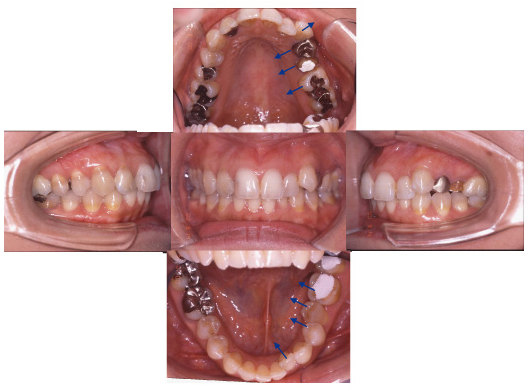

治療前-治療後

(治療前:写真左)

態癖の影響が強く奥歯が舌側に傾斜し、八重歯になっています。

(治療後:写真右)

矯正治療をおこない歯列を整え、金属の詰め物はセラミッククラウンに換えて咬み合わせを再構成しました。

三本の小臼歯を抜歯していますが、歯並びを小さくしないようにしています。